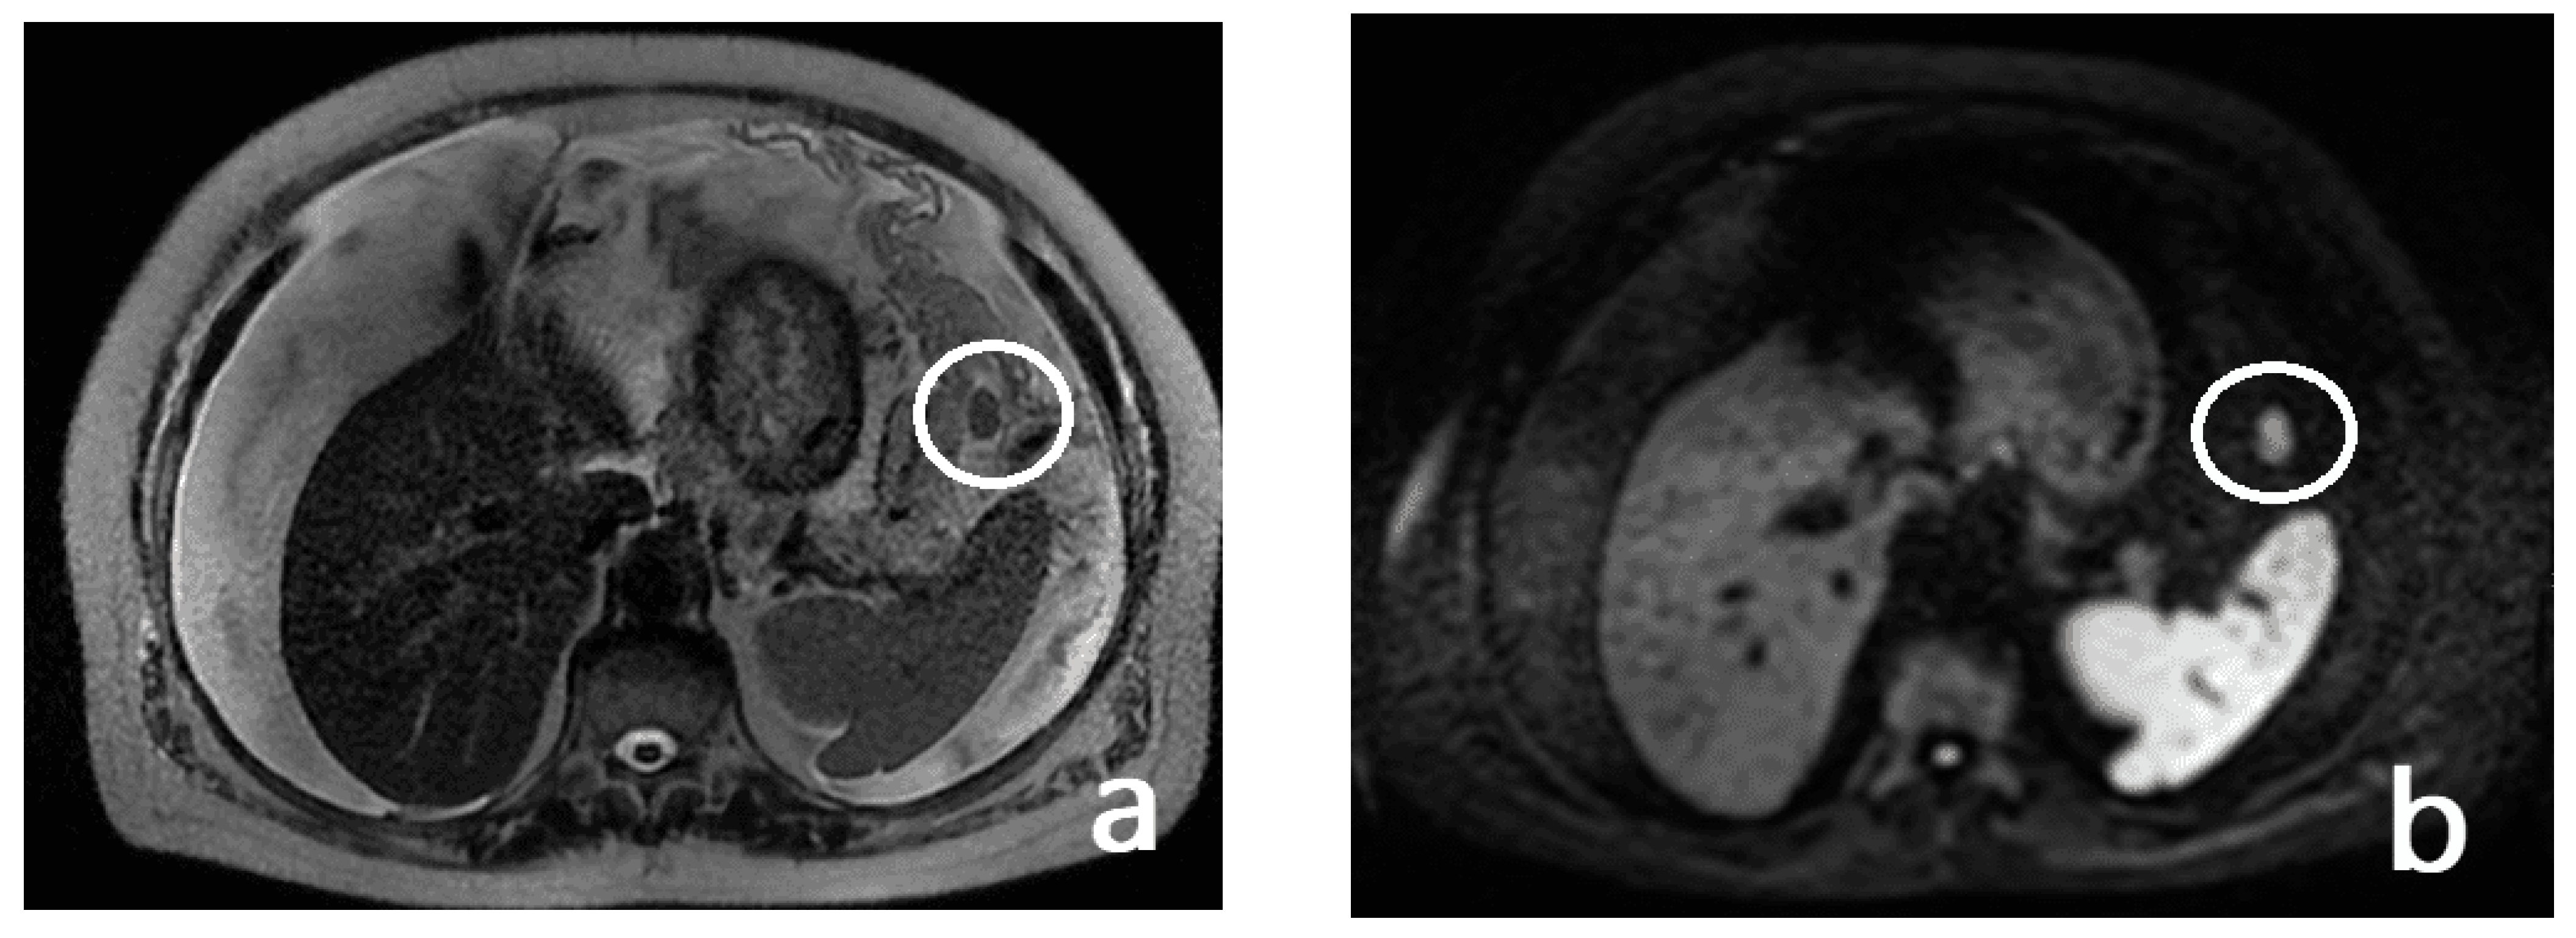

- Mesenteral root involvementDisease in the small bowel and intestinal mesentery constitutes a sentinel and limiting criterion in decision making in CRS. Therefore, the evaluation of small-bowel loops and their mesentery should be a key component in the preoperative imaging evaluation of a patient with PC [24]. The diffuse involvement of the mesentery root is, in fact, a criterion for unresectability. Thin mesenteral tumor sheets are invisible on CT and PET scans [111]. In a study of 30 cases by Dromain et al. [87], CT detected implants in the small bowel in 26% of cases, whereas the true incidence of this disease location at the time of surgery was 83%.Furthermore, MRI has been reported to be superior to CT in the evaluation of the intestinal tract and mesenteric involvement in light of its high capacity in soft-tissue studies [112].Diffuse small-bowel involvement (mesentery and/or intestinal serosa) remains difficult to represent, however, and when present, the radiologist should estimate the extent of involvement as less than or greater than 50%. The radiologist should also describe the number and location of any stenosis of segments of the small intestine, as well as invasion of the colon or gastric system, to produce a complete analysis of the entire digestive tract [69].Indeed, Jacquet et al. [43] found that when preoperative CT showed a tumor causing intestinal obstruction, surgical cytoreduction was suboptimal in 88% of cases. If the tumor obstructing the jejunum or superior ileum was greater than 5 cm in diameter, no subject had a complete CRS.In fact, the two radiologic findings that Sugarbaker et al. [113] reported as most strongly associated with poor outcomes in CRS are the presence of tumor nodules greater than 5 cm on small-bowel surfaces and segmental small-bowel obstruction.Preoperative imaging can aid in patient selection by avoiding surgery for patients whose tumors are excessively large for adequate surgical cytoreduction; in particular MRI using gadolinium and DWI sequences routinely describe tumor-cell sheets involving the serosa of the small intestine and mesentery, which are typically not seen on CT or PET [55] (Figure 14 and Figure 15).